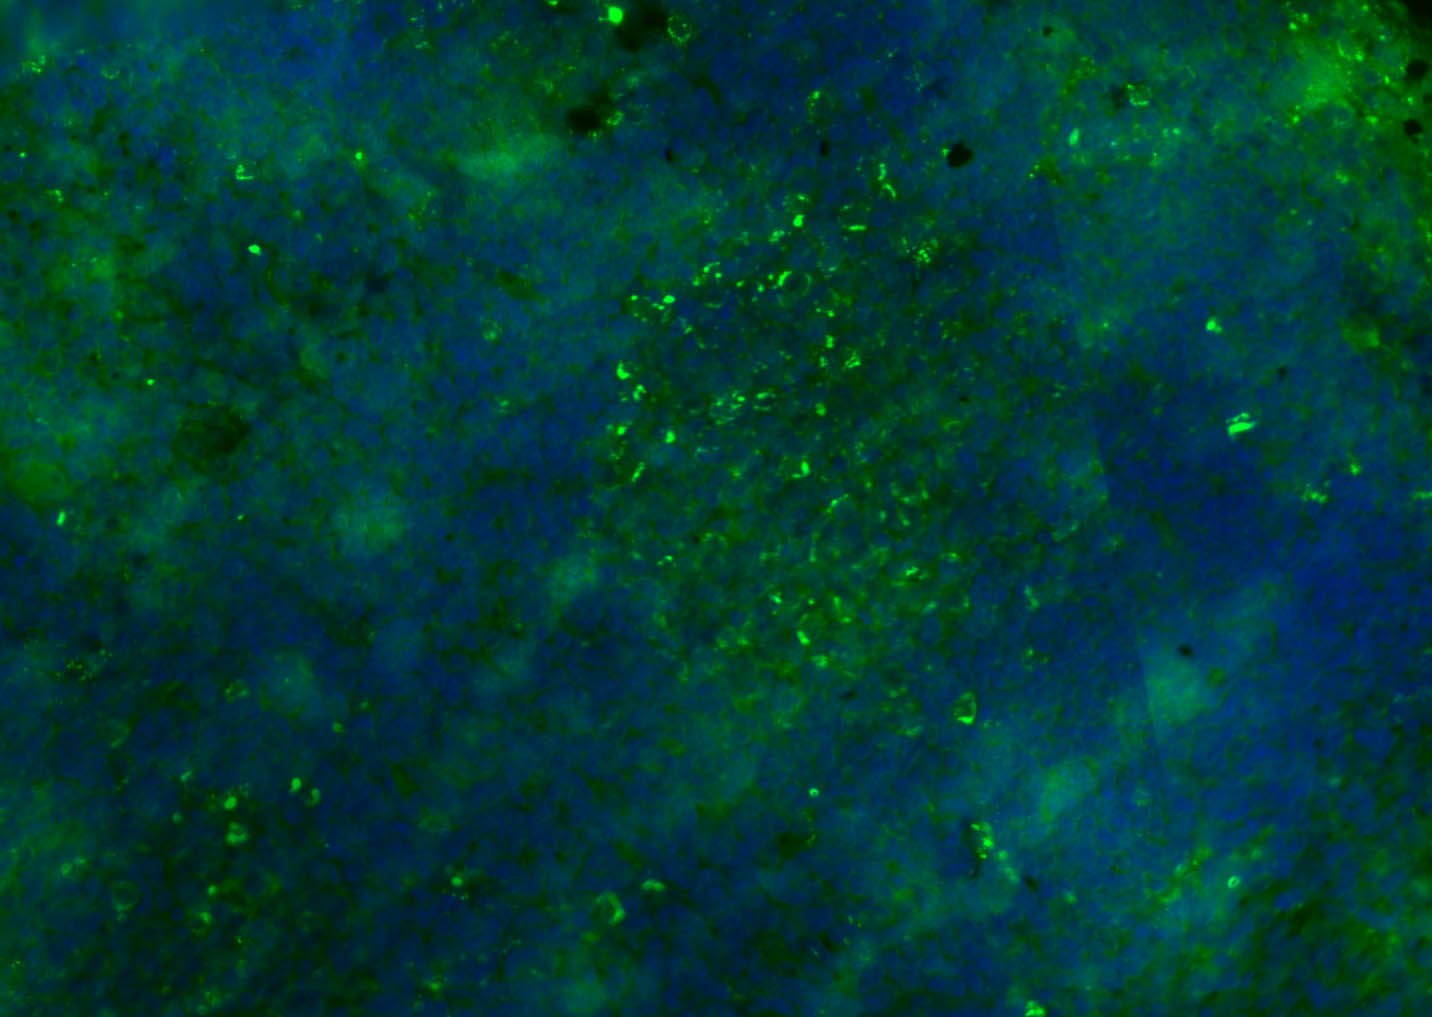

Paraformaldehyde-fixed, paraffin embedded (human tonsil); Antigen retrieval by boiling in sodium citrate buffer (pH6.0) for 15min; Blocking buffer (normal goat serum) at 37°C for 30min; Antibody incubation with (CD8B) Polyclonal Antibody, Unconjugated (bs-4914R) at 1:200 overnight at 4°C, followed by a conjugated Goat Anti-Rabbit IgG antibody (bs-0295G-FITC) for 90 minutes, and DAPI for nuclei staining.